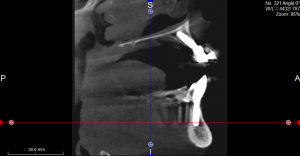

Röntgenplanung mittels OPTG und DVT ( Digitaler Volumentomographie ) : Bohrschablone :